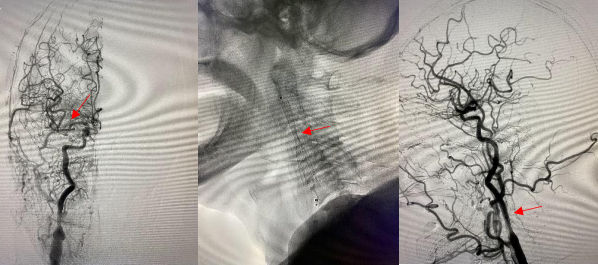

头颈部血管造影提示:患者为右侧颈内动脉极重度狭窄合并右侧大脑中动脉闭塞。

由远及近,优先开通右侧大脑中动脉恢复颅内血流,再行右侧颈内动脉起始部支架植入血管成形,顺利开通闭塞血管,颅内血流恢复。